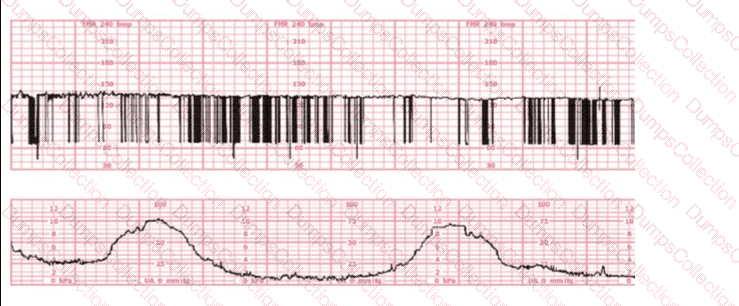

Prenatal diagnosis shows that a fetus has renal agenesis. During delivery, what type of electronic fetal heart rate pattern is most likely to be seen due to a common complication associated with this syndrome?